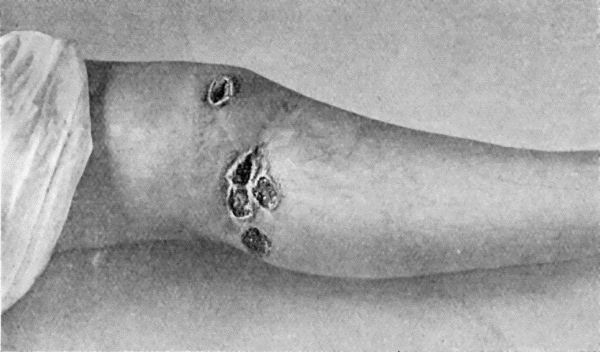

17.Syphilitic Ulcers in region of Knee 76

18.Callous Ulcer showing thickened edges 78